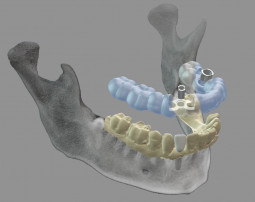

Dental Wings’ DWOS® coDiagnostiX™ 9.0 creates a new opportunity for practioners and labs to collaborate on implant case planning and execution. Labs can design and produce 3D printed surgical guides, as well as provisionals before surgery.

The coDiagnostiX software is available in Europe and North America and in process for Latin America.